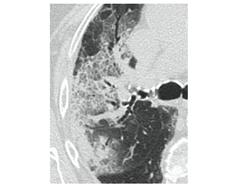

2. Наличие клинических проявлений, указанных в п. 1, в сочетании с характерными изменениями в легких по данным компьютерной томографии (КТ) (см. Приложение 1 настоящих рекомендаций) вне зависимости от результатов однократного лабораторного исследования на наличие РНК SARS-CoV-2 и эпидемиологического анамнеза.

- Изменения при КТ (рентгенографии), типичные для вирусного поражения (объем поражения минимальный или средний; КТ 1-2)

- Изменения в легких при КТ (рентгенографии), типичные для вирусного поражения (объем поражения значительный или субтотальный; КТ 3-4)

- Изменения в легких при КТ (рентгенографии), типичные для вирусного поражения критической степени (объем поражения значительный или субтотальный; КТ 4) или картина ОРДС.

КТ имеет высокую чувствительность в выявлении изменений в легких, характерных для COVID-19. Применение КТ целесообразно для первичной оценки состояния ОГК у пациентов с тяжелыми прогрессирующими формами заболевания, а также для дифференциальной диагностики выявленных изменений и оценки динамики процесса. КТ позволяет выявить характерные изменения в легких у пациентов с COVID-19 еще до появления положительных лабораторных тестов на инфекцию с помощью МАНК. В то же время, КТ выявляет изменения легких у значительного числа пациентов с бессимптомной и легкой формами заболевания, которым не требуется госпитализация. Результаты КТ в этих случаях не влияют на тактику лечения и прогноз заболевания при наличии лабораторного подтверждения COVID-19. Поэтому массовое применение КТ для скрининга асимптомных и легких форм болезни не рекомендуется.